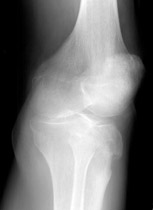

Lateral Tibial Plateau Fracture

• Plateau fractures (medial and lateral) are the most common fracture sustained at the proximal tibia.

• When depression is not present, fracture may be difficult to recognize with standard radiographic exam. Alternative views and/or CT may be required for diagnosis.

• Associated damage to the anterior cruciate ligament, medial collateral ligament and medial meniscus is common due to valgus stress placed on the knee during injury.